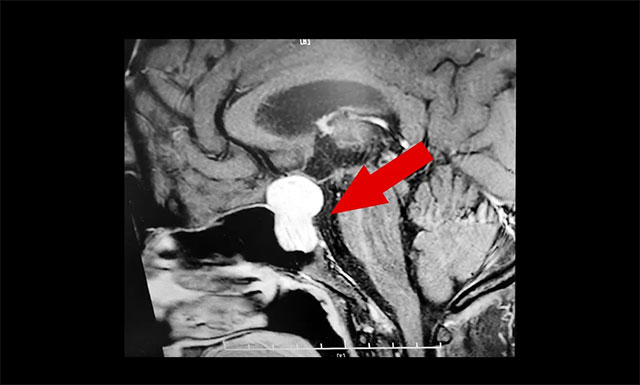

隨后,患者進行了頭部鞍區(qū)MRI平掃+增強,結果顯示:蝶鞍顯著擴大,鞍區(qū)見一典型的“8字”狀腫物,大小約2.2×1.8×2.7cm,病變像鞍上生長,占據鞍上池,推移視交叉;向下生長,鞍底骨質受壓變薄;向鞍旁生長,侵及海綿竇、局部包裹約1/3。

▲ 術前MR影像:腫瘤向鞍內、鞍上、鞍旁發(fā)展,呈“啞鈴形”

潘仁龍主任指出,垂體腫瘤向鞍上生長,占據鞍上池,壓迫到視神經傳導物,使患者視物出現異常。一般1-3cm的大腺瘤或大于3cm的巨大腺瘤,都會引起不同程度的視力問題。

李士其教授、潘仁龍主任、吳治群博士會診后指出:腫瘤主體位于鞍內、鞍上、鞍旁發(fā)展,呈“啞鈴”形。從影像學資料上看,發(fā)現瘤體已經非常大了,屬于垂體大腺瘤。瘤體占據鞍區(qū),并向蝶竇和鞍上發(fā)展,侵襲海綿竇,視神經、視交叉受壓,所以需要馬上進行手術切除,解除壓迫。若任其發(fā)展,將來有失明的風險。